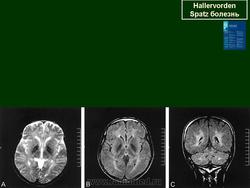

ГМ. Галлервордена - Шпатца болезнь. +

Галлервордена - Шпатца болезнь

Болезнь Галлервордена - Шпатца - наследственное заболевание экстрапирамидной системы, связанная с нарушением обмена железа и липидов и повреждением бледного шара и черной субстанции. Тип наследования аутосомно-рецессивный. При патоморфологическом исследовании характерным признаком является гиперпигментация бледного шара и черной субстанции. Обнаруживается пигментация коры полушарий большого мозга и таламуса. Пигмент находится внутри невронов и глиальных клеток, расположенных около сосудов; содержит железо (вместе с тем каких-либо нарушений обмена железа в организме не обнаружено). Наблюдаются утолщение и фрагментация аксонцилиндров в пораженных областях. Постепенно наступает дегенерация невронов коры полушарий большого мозга и мозжечка. Характеризуются нарастающей экстрапирамидной ригидностью, гиперкинезами (атетоз, торсионная дистония), затем развивается акинетико-ригидный синдром, пирамидная микросимптоматика, снижение интеллекта. Течение медленно прогрессирующее на протяжении 10 - 20 лет.

"Глаз тигра"-наглядно и красиво.

Вы правы. Выставил еще более нагладные исллюстрации.